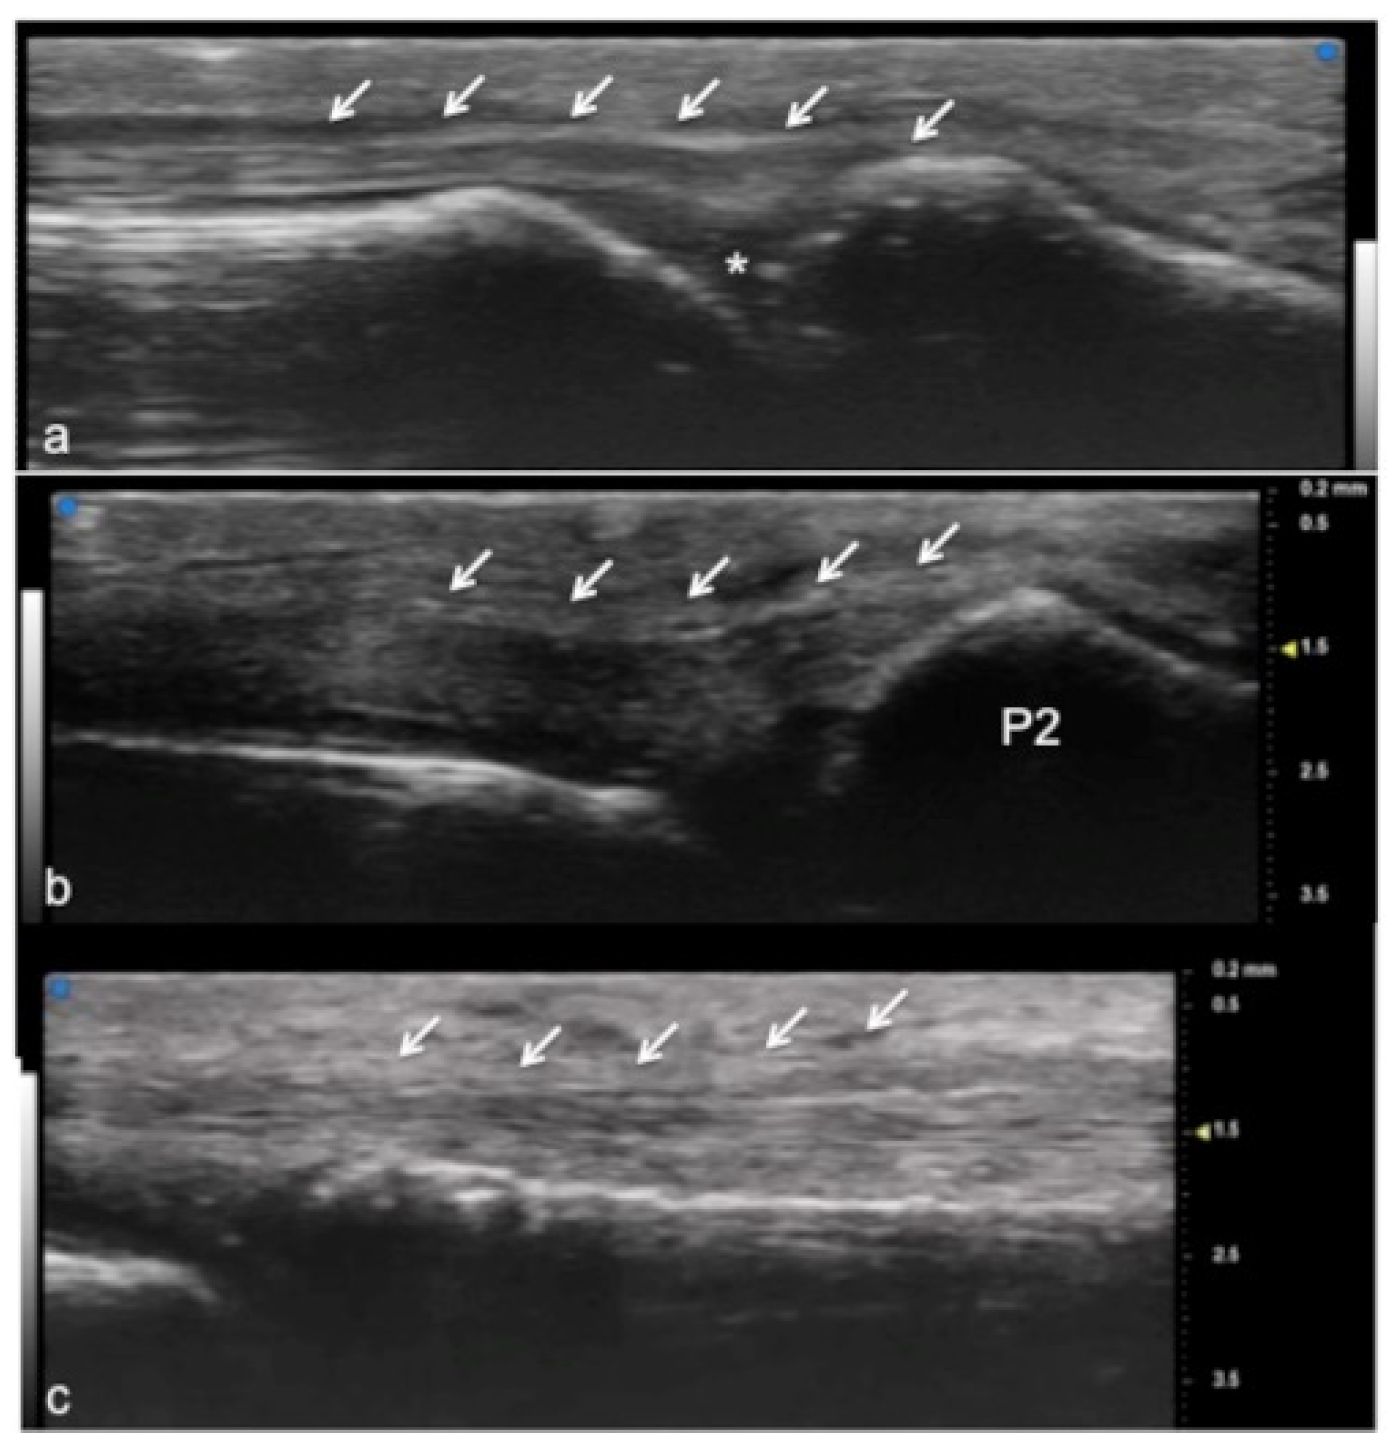

Figure 2.

Extensor tendon of a finger. UHFUS gives a detailed and magnified representation of small structures such as the extensor tendon of the finger, even allowing the visualization of partial lesions. In (a), the sagittal view of the terminal extensor tendon (white arrows) at the level of the distal interphalangeal joint (white asterisk). In (b), the median band of the extensor tendon inserting at the level of the middle phalanx (P2). In (c), the thin sagittal band of the extensor tendon at the level of the metacarpal head.

Figure 3.

Flexor tendon of a finger. Using UHFUS at the flexor tendons, the same spatial resolution can be achieved as in the imaging of the extensor tendons. In (a), the sagittal view of the deep flexor tendon component inserting on the basis of the distal phalanx (P3). In (b), the superficial component of the flexor tendon (white arrows) lying near the deep component (white square parenthesis).